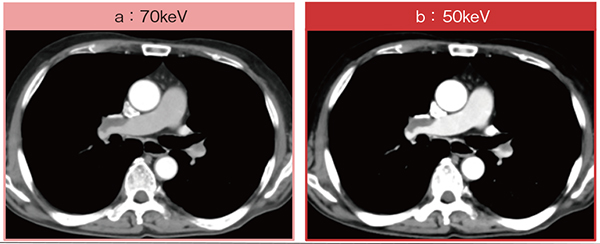

症例5は,80歳代,男性,肺動脈塞栓症の症例である。労作時酸素化低下とD-dimerの上昇を認め,肺動脈塞栓の有無の評価目的で造影CTが施行された。検査開始後30秒で造影剤注入装置の圧力上昇が検知され,血管外への造影剤漏出を認めたため検査を中断。その後,対応を行った上で再度CT撮影を行った。70keV画像(図7 a)では右の肺動脈に血栓を認めるものの,造影効果はやや不十分であるが,50keV画像(図7 b)では肺動脈内の造影効果が向上し,特に左肺動脈の血栓がより明瞭となっている。PCD-CTでは,通常の撮影と同時にSpectral Imagingが可能なため,造影剤量が不十分な撮影においても診断に寄与する画像の取得が期待できる。

図7 症例5:肺動脈塞栓症疑い症例におけるSpectral Imagingによる造影効果の向上